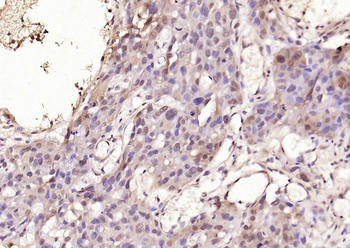

Phospho-Smad3 (Ser423 + Ser425) Rabbit Polyclonal Antibody [orb6983]

FC, IF, IHC-Fr, IHC-P, WB

Bovine, Canine, Equine, Gallus

Human, Mouse, Porcine, Rat

Rabbit

Polyclonal

Unconjugated

100 μl, 200 μl, 50 μlSMAD7 Rabbit Polyclonal Antibody [orb500819]

FC, ICC, IF, IHC-Fr, IHC-P, WB

Bovine, Porcine

Human, Mouse, Rat

Rabbit

Polyclonal

Unconjugated

100 μl, 200 μl, 50 μlPhospho-Smad3 (Ser213) Rabbit Polyclonal Antibody [orb106193]

FC, IF, IHC-Fr, IHC-P

Bovine, Equine, Gallus, Guinea pig, Rabbit, Sheep

Human, Mouse, Rat

Rabbit

Polyclonal

Unconjugated

50 μl, 100 μl, 200 μl